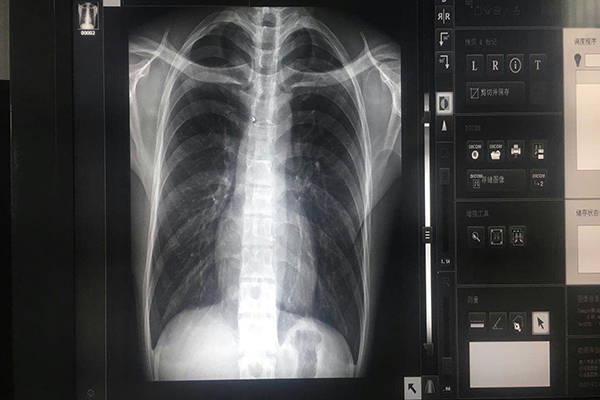

亮度就是灰階顯示器上顯示圖像有多么明亮,顯示越明亮圖像中的能夠產(chǎn)生的動態(tài)范圍就越大,使人們在圖像中分辨更多的色調(diào),這種動態(tài)范圍必須提供全8bit灰階圖像(即256不同色調(diào))。